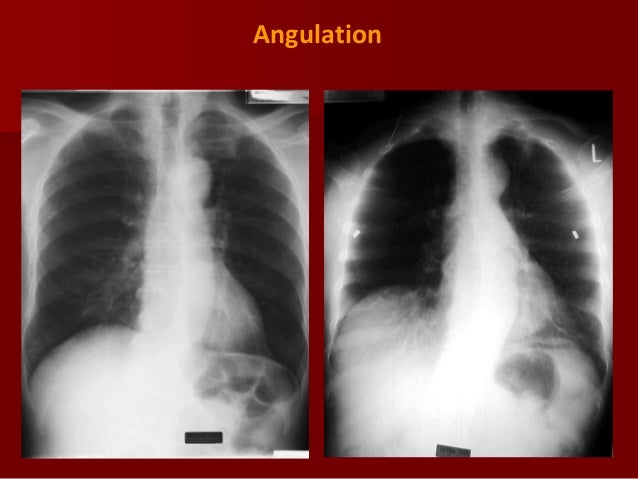

Ap vs pa view. Abc news is your trusted source on political news stories and videos. Note the ap sitting label. It is utilized in many imaging contexts including trauma postoperatively and for chronic conditions. The pa posterioranterior film is obtained with the patient facing the cassette and the x ray tube 6 feet away.

Usually bedridden and infants. In simple words during the procedure of taking x ray radiograph when x ray passes from posterior of body to anterior it is called pa view. Ap erect view chest supine view 10. Ap kevin harvick was a sure bet to make the nascar finale and likely close out one of the most dominant seasons of the decade.

Ap projection images are of lower quality than pa images. Compare this image with the pa view below. Ap projection example. Clavicle remains at top of lung field 2.

Clavicle in lung field 2. Patient position the patient is erect or supine dependin. Ribs lie more horizontal 3. Differences in pa versus ap projection on a chest radiograph.

The heart appears enlarged a combination of ap magnification and underinflation. Heart shadow looks larger 5. Like all methods of radiography chest radiography employs ionizing radiation in the form of x rays to generate images of the chest. A chest radiograph called a chest x ray cxr or chest film is a projection radiograph of the chest used to diagnose conditions affecting the chest its contents and nearby structures.

Scapula comes in the lung field 4. Heart shadow smaller 5. While in ap view the direction is opposite. Get the latest coverage and analysis on everything from the trump presidency senate house and supreme court.